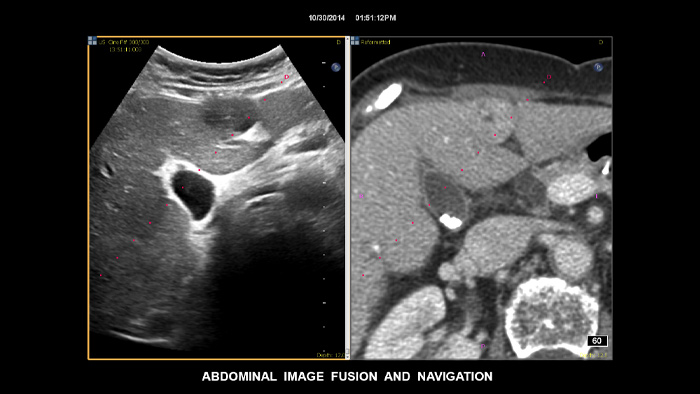

Prenez des décisions en toute confiance, même dans les cas de diagnostic difficiles, en vous appuyant sur notre outil de fusion d'images et de navigation par aiguille. Le flux de travail rationalisé vous permet de réaliser une fusion rapide et efficace des modalités CT/MR/PET avec l'échographie en temps réel. La navigation avec tracking de l'aiguille offre des facilité de guidage de la biopsie de petites lésions difficiles d'accès2.